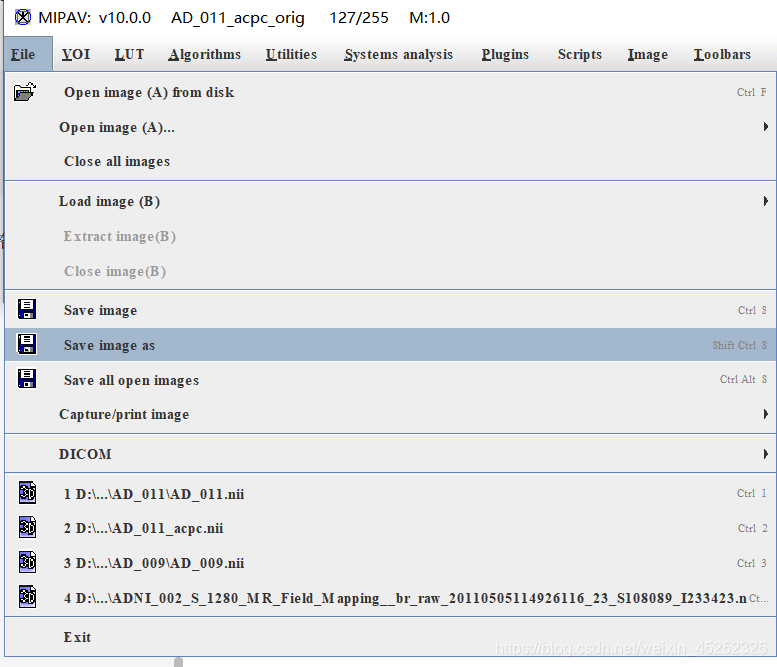

(7)保存:在主界面上点击file-save image as,然后选择要保存的格式,进行图片保存

一般选择nii格式